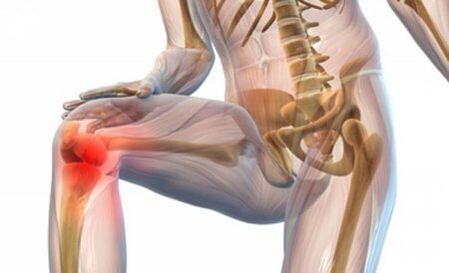

L'inflammation, suivie d'une destruction grave, ainsi que par déformation, est appelée arthrose de l'articulation du genou, dont les symptômes et dont le traitement peut varier considérablement selon le stade. Cette maladie est assez courante et les personnes de nationalités différentes sont malades. Comprenons ensemble: quelle est cette maladie, quelles raisons apportent-elles directement à son occurrence, quels diagnostics devraient être approuvés?

Quelle est l'arthrose des articulations du genou? C'est peut-être l'option la plus courante, qui est appelée gonartrose. Dans ce cas, les changements conjoints apparaissent, tandis que les gens souffrent après 45 ans. Les femmes tombent malades plus souvent que les hommes. Fondamentalement, diverses blessures à la gonartrose sont libérées ou si une personne passe beaucoup de temps à se tenir debout. Bien sûr, la raison principale est le vieillissement naturel du corps. Très souvent, les personnes en surpoids et l'expansion des varices souffrent.